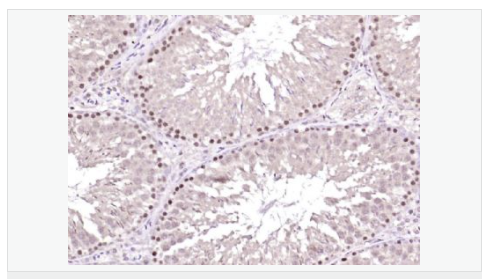

| 產品應用 | ELISA=1:5000-10000 IHC-P=1:100-500 IHC-F=1:100-500 IF=1:100-500 (石蠟切片需做抗原修復) not yet tested in other applications. optimal dilutions/concentrations should be determined by the end user. |